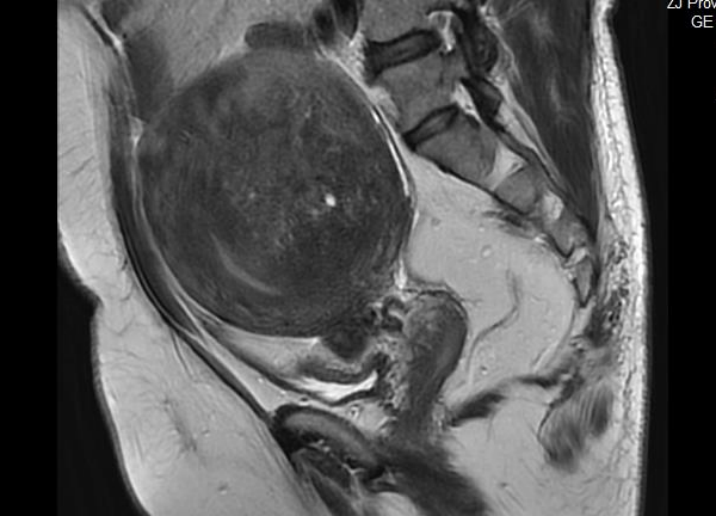

病史介绍 患者李女士,41岁,2024年11月21日就诊 主诉:进行性痛经伴月经增多10年 现病史:患者平素月经规律,月经周期28天-30天,经期7-9天,有痛经,近10年月经前3天痛经程度较重,且逐渐加重,持续4-5天,呈下腹坠痛,深部绞痛,末次月经疼痛VAS评分8分,口服布洛芬稍缓解;月经量逐步增多,经量多时每天需4片成人纸尿裤。8月余前外院放置曼月乐环后自行脱落。外院B超检查提示子宫后壁肌层内探及一不均回声区,大小约6.9cm*5.6cm*4.8cm。子宫局灶性腺肌症伴腺肌瘤形成。初步诊断“子宫腺肌症、剖宫产个人史”。 既往史:既往体健,否认慢性及传染性疾病,2018年行剖宫产术分娩,手术后恢复好。 月经史:13岁初潮,月经周期28天-30天,经期7天-9天,伴痛经(VAS评分8分),经量多,较多时每天需4片成人纸尿裤。 婚育史:已婚已育,1-0-0-1,既往剖宫产史。 家族史:否认家族中有遗传性疾病史。 体格检查:体重:59.2Kg,身高:160cm,BMI23.1,体温:36.6℃,脉搏:86次/分,呼吸:17次/分,血压:119/71mmHg,生命体征平稳,贫血貌,无痤疮,无多毛;乳腺未触及明显包块;余体检无殊。 妇科检查: 外阴、阴道无特殊,宫颈轻度柱状上皮外延,无举痛,子宫前位,子宫如孕3+月大,轻压痛,活动度偏差,质地硬,表面尚光滑,右侧附件区未及明显异常,左侧附件区有压痛略增厚,盆底未触及明显触痛结节。 辅助检查: 1、经阴道超声检查:子宫腺肌症伴腺肌瘤形成考虑,子宫前位,后壁肌层回声增粗,分布不均匀,范围约6.9cm*5.6cm*4.8cm,边界欠清,内见点条状血流信号;双层内膜厚度0.8cm,回声均匀;盆腔积液,后盆腔暗区1.6cm,透声好; 初步诊断: 1、子宫腺肌病; 2、子宫腺肌瘤; 3、轻度贫血; 4、剖宫产个人史。 诊断依据: 1、进行性痛经伴月经增多10年; ①经阴道超声检查:子宫腺肌症伴腺肌瘤形成考虑; ②CA 125:142.8↑U/ml; ③盆腔MRI平扫:子宫体积增大,子宫壁增厚,以子宫后壁为著,局部呈团块状,结合带增厚、边界显示不清,双侧卵巢大小欠对称,右侧较左侧稍饱满,约20mm*15mm。考虑子宫腺肌症伴腺肌瘤形成。 诊疗经过 诊疗思路:患者已婚已育,无再生育需求,根据病史、查体及辅助检查提示子宫腺肌病、子宫腺肌瘤,且病情较重,明显影响生活质量。 1.初次治疗分析与方案: 手术治疗:疼痛症状严重且月经过多,导致贫血,有手术指征。 药物治疗: (1)非甾体抗炎药,效果不佳,子宫腺肌病病理生理持续进展; (2)口服避孕药,患者年龄大于40岁,安全性下降、全身副作用增加; (3)GnRH-a,短期应用可行,长期应用受限; (4)孕激素(曼月乐脱落,不适合此患者;地诺孕素或地屈孕酮可行)经过和患者详细沟通病情,交待手术和药物治疗的利弊,患者知情,意愿先行药物治疗,选择药物治疗方案:地诺孕素2mg qd全周期口服。 2.第一次随访: 3.手术治疗: 行腹腔镜下子宫腺肌病灶切除术+腹腔镜子宫内膜异位病灶烧灼术+肠粘连松解术。 腹腔镜探查:部分肠系膜与腹壁粘连,子宫前位,增大如孕3+月,子宫后壁均匀增大,外凸明显;右侧输卵管及双侧卵巢外观未见异常,右侧输卵管伞端可见输卵管系膜囊肿大小约0.3cm。子宫表面可见散在紫蓝色内异结节,道格拉斯窝存在。探查余盆腹腔未见异常。下图所示分别为术前、术中、术后照片。 术后病理: 1、“子宫肿块”子宫腺肌症; 2、“左侧输卵管系膜囊肿”副中肾管囊肿。 术后处理:考虑患者术前使用地诺孕素有脱发副作用,患者无法接受。术后予地屈孕酮全周期治疗,服药方法:地屈孕酮20mg qd po治疗。 4.术后第一次随访: 5.术后第二次随访: 6.术后第三次随访: 1、本例患者就诊时年龄41岁,其临床症状主要以疼痛进行性加重,月经过多导致贫血,体检子宫明显增大,经阴道超声及盆腔磁共振提示:子宫腺肌症伴腺肌瘤形成考虑。CA 125:142.8↑U/ml。因此,临床诊断子宫腺肌病成立。治疗方案的选择根据临床症状、腺肌病灶大小的情况,选择手术治疗是较好的方案,但患者起初更希望药物治疗,交待病情及治疗风险后选择药物治疗,并且密切随访。 因子宫腺肌病雌激素依赖性,需要长期药物治疗,因此需有效安全且耐受性好的药物,持续使用到绝经。综合考虑后选择地诺孕素,随访后发现脱发明显,患者改选手术治疗,手术顺利。地屈孕酮对于异位病灶组织有显著抗增殖、促凋亡 2、手术治疗在子宫腺肌病治疗中的作用 全子宫切除的价值在于“一劳永逸”根治子宫腺肌病,然而子宫切除术不仅给妇女带来生理器官的缺失,可能造成卵巢功能减退、盆底功能障碍而影响患者的生活质量,而且可能造成心理伤害,尤其年轻或有生育要求的患者更是难以接受。 保留器官手术包括局灶性子宫腺肌病的子宫腺肌瘤剔除术、弥漫性子宫腺肌病病灶减少术等。其适应证为:有生育要求者、药物治疗失败希望保留子宫或对于药物治疗有禁忌证的患者。主要的手术原则包括:切除病变组织,尽量保留子宫肌层的强度和完整性,避免破坏子宫内膜腔,尽量减少浆膜损伤,保持输卵管的完整性,并对子宫肌层进行多层缝合[1]。对于保育患者尽量使用“冷器械”。 子宫腺肌病灶的切尽程度与术后病情密切相关,平衡病灶的去除程度、术中手术难度(如子宫创面的缝合、子宫重塑形)、术后恢复及子宫腺肌病病情的持续及远期复发、再妊娠患者的妊娠相关并发症是手术治疗及后续长期管理的难点。 3、子宫腺肌病病灶切除术后长期管理的意义 保留子宫手术后复发的预防子宫腺肌病保留子宫的手术后1年内复发率2.8%-14%,术后2年内复发率14.3%-49.0%[2]。子宫腺肌病术后需要长期管理,可以根据患者年龄、临床症状、有无生育要求、病变类型以及药物特点进行个体化治疗。本例患者术后管理方案为地屈孕酮20mg qd po全周期治疗,痛经及月经过多症状达到治愈效果。 术后长期管理是基于子宫腺肌病的多发性以及术后的高复发和迁延性,其术后管理的目的在于促进康复,减轻负担,降低并发症,提高生活质量。子宫腺肌病严重威胁女性健康,增加公共卫生负担。国内共识提出了子宫腺肌病的三级管理模式,实现全疾病周期的精准化和个体化管理,从而希望达到以下目标:预防其发生,延缓其进展,减轻其危害,防止其复发[3]。 参考文献: [1]Horng HC, Chen CH, Chen CY, Tsui KH, Liu WM, Wang PH, Chang WH, Huang BS, Sun HD, Chang TC, Chang WC, Yen MS. Uterine-sparing surgery for adenomyosis and / or adenomyoma. Taiwan J Obstet Gynecol. 2014;53(1):3-7.

4、盆腔MRI平扫:子宫体积增大,子宫壁增厚,以子宫后壁为著,局部呈团块状,结合带增厚、边界显示不清,TIWI呈等信号,T2WI呈低信号,其内可见局灶性高信号,DWI呈不均匀稍高信号,ADC呈等信号。双侧卵巢大小欠对称,右侧较左侧稍饱满,约20mm*15mm。盆腔内未见明显肿大的淋巴结。盆腔内少许积液。提示:子宫腺肌症伴腺肌瘤形成,必要时增强检查。所示双侧卵巢欠对称,右侧较左侧稍饱满,请结合临床、随诊。